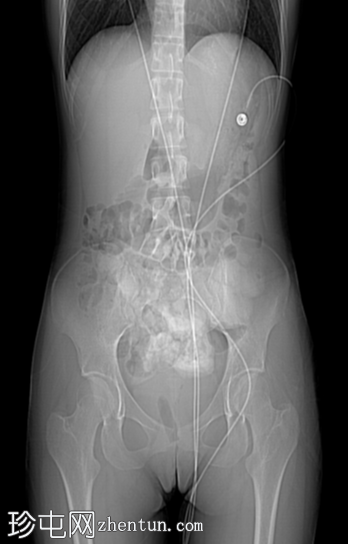

定位片

1.png

定位片、轴位、矢状位及冠状位图像均可见阴道内有一根线状充气棉塞。棉塞的线头在本例中清晰可见。